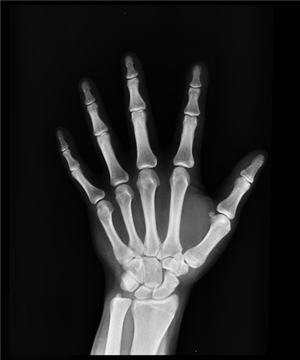

Taller per a un envelliment òssia saludable

Docent: Jone Montiel Higuero, Fisioterapeuta del Centre de Salut Sant Vicent 2. Coordina: Adela Alonso Gallegos, Infermera comunitària. Inscripció gratuïta disponible a partir del 29 d'octubre a les #9:30 h. Calendari: 7, 14, 21 i 28 novembre de 2025. Organitza: Aula de Salut de la Seu Universitària Ciutat d'Alacant.